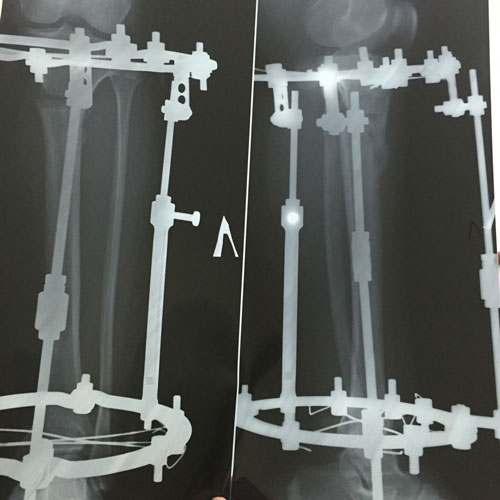

рентген в 90 дней.

Здравствуйте, Б.! Сращение идёт хорошо, но Вам ходить ещё месяц. в 120 дней ждём рентген.